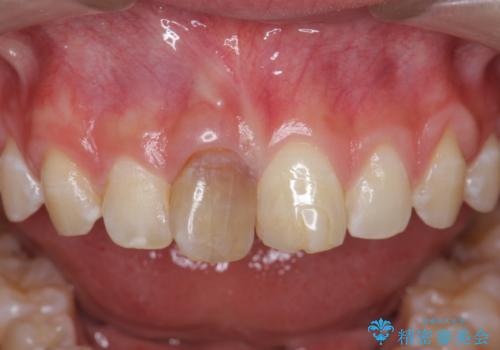

前歯をきれいにしたい ジルコニアクラウンによる審美治療

- 前歯の見た目の改善を求めて来院されました。

ジルコニアクラウンによる審美性の改善を計画します。

今回失活歯であったため捻転を取り反対側の前歯に揃えて補綴を行うことができました。